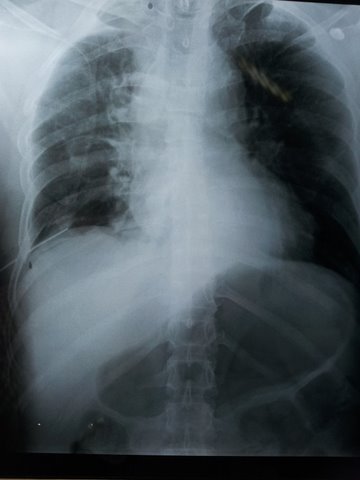

XRAYS-

The above x-ray shows tension pneumothorax on the RT side and B/L Humerus fractures.

The above x-ray shows the ICD inserted in the RT 6th intercostals space and developing pneumothorax in the LT side.